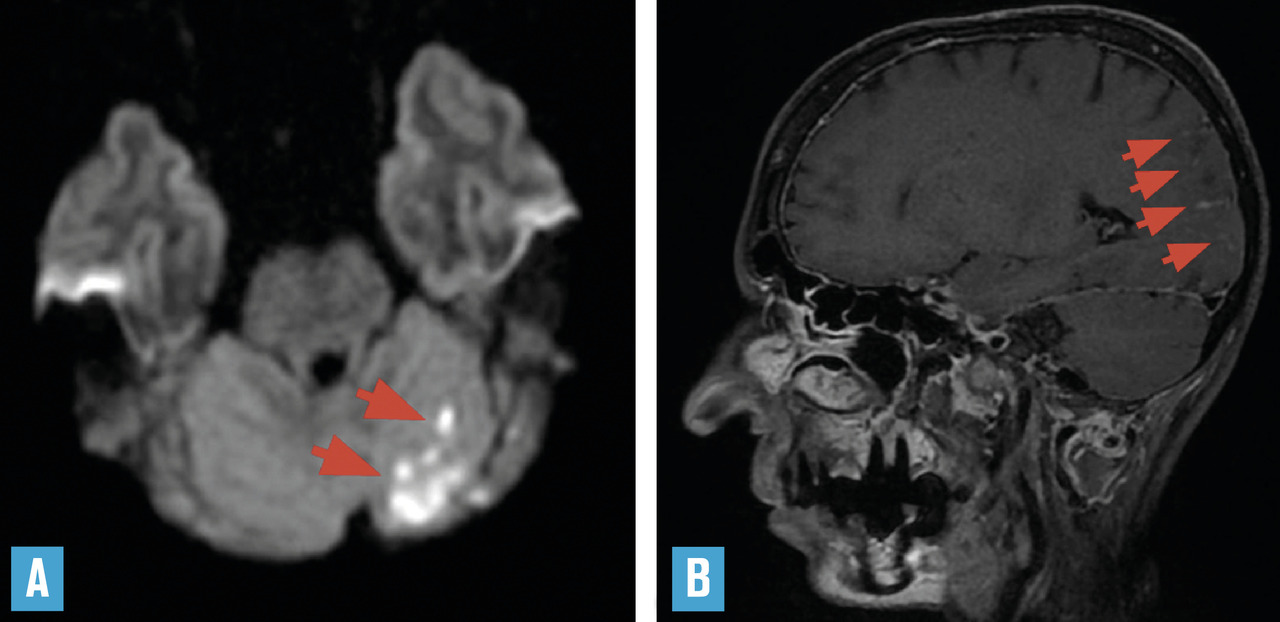

La tomodensitométrie n’a que peu d’intérêt tant sa sensibilité et sa spécificité sont faibles. L’imagerie par résonance magnétique (IRM) est donc indispensable. Aucune anomalie n’est spécifique, mais leur combinaison renforce la suspicion de vascularite (– de lésions parenchymateuses multiples : infarctus corticaux ou profonds dans des territoires différents, hémorragies cérébrales symptomatiques ou non (« microbleeds »), anomalies confluentes de la substance blanche ;

– de prises de contraste corticales et surtout leptoméningées, témoignant de l’atteinte inflammatoire (

Des présentations radiologiques trompeuses ont été rapportées, telles qu’une large lésion unique d’aspect pseudotumoral, ou encore un aspect de leucoencéphalopathie postérieure. La sensibilité élevée de l’IRM pour déceler des anomalies intracérébrales de petite taille peut être source de difficulté : la présence d’hypersignaux de la substance blanche en séquences T2/FLAIR (leucoaraïose), fréquente dans de nombreuses circonstances, ne doit pas être interprétée trop facilement comme étant un signe de vascularite. Outre les signes parenchymateux sus-décrits, il peut exister en séquence FLAIR (sans injection) une hyperdensité d’artères corticales, témoignant d’un ralentissement circulatoire du fait de sténoses distales. L’exploration parenchymateuse est complétée par une angiographie par résonance magnétique (ARM) intracrânienne pour étudier le polygone de Willis et les premiers centimètres de ses branches de division (

Les cohortes récentes fixent la mortalité de la maladie à moins de 10 % à 5 ans.3, 4 Les mêmes travaux ont permis de dégager un certain nombre de facteurs pronostiques : la présence d’un ou plusieurs infarctus cérébraux sur l’imagerie initiale, l’atteinte des artères intracrâniennes de gros ou moyens calibres (premiers centimètres au-delà du polygone de Willis) sont de mauvais pronostic, tandis que les prises de contraste parenchymateuses et surtout méningées témoignent d’un risque élevé de rechute à l’arrêt des traitements. Ces trois constatations poussent donc à un traitement agressif, superposable à celui proposé dans les vascularites systémiques extensives : association d’une corticothérapie à fortes doses (volontiers par bolus de 500 à 1000 mg initialement) et d’immunosuppresseurs pendant 6 mois, suivie d’un traitement d’entretien.7 Le cyclophosphamide est l’immunosuppresseur recommandé en induction (protocole proposé : bolus de 0,6 g/m2 à J1, J15 et J30, puis 0,7 g/m2 toutes les 3 semaines). L’importance d’un traitement immunosuppresseur d’entretien pendant au moins 12 à 18 mois est démontrée,7 en utilisant le plus souvent le rituximab (anti-CD20) ou le mycophénolate mofétil. Ce dernier semble particulièrement intéressant dans les formes pédiatriques de vascularite primitive du système nerveux central, où le niveau d’inflammation artérielle est très élevé.8

Les difficultés diagnostiques d’une vascularite primitive du système nerveux central se retrouvent lorsqu’il s’agit d’évaluer la possibilité de diminuer les doses thérapeutiques. Auparavant, il convient de juger de la stabilité de l’atteinte inflammatoire sur des arguments cliniques (disparition des céphalées, absence de symptôme neurologique focal récent), biologiques (normalisation du LCR) et radiologiques (disparition des prises de contraste, absence de nouvelle lésion à l’IRM et stabilisation des anomalies artérielles, en sachant que des sténoses séquellaires sont possibles). Un suivi strict par IRM et examens radiologiques est indispensable.